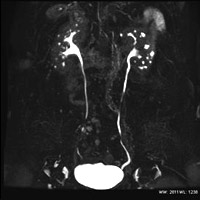

造影剤を使用しない尿路検査